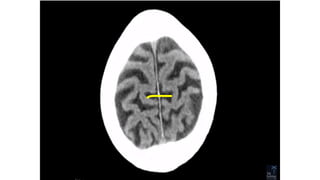

• Flax

THE MENINGES

1. Using spin-echo sequences

2. The dura mater may be recognized as a short,

intermittent, thin, hyperintense, curvilinear structure on

contrast-enhanced T1-weighted MRI.

3. The pia mater and the arachnoid mater do NOT enhance

in normal subjects